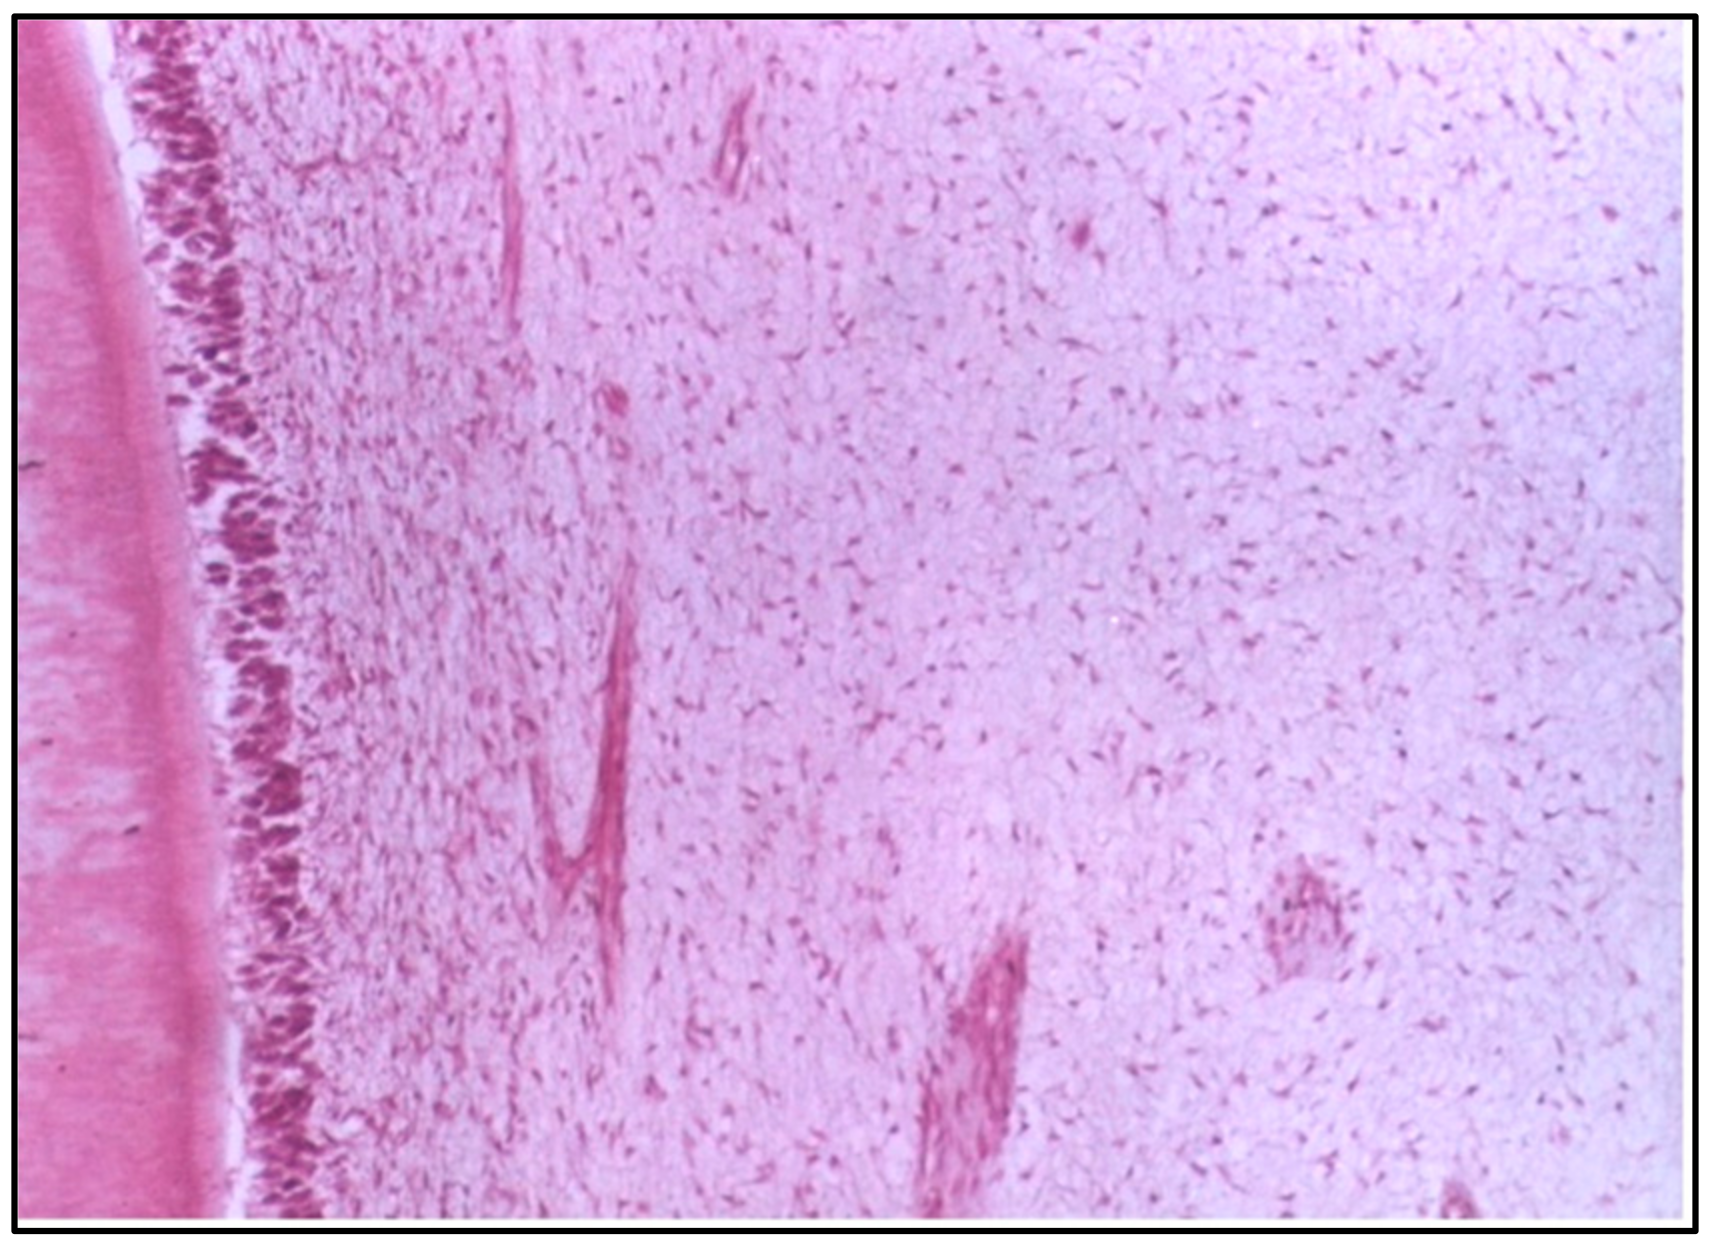

At 6 weeks, the pulp tissue exhibited more pronounced destructive changes. The central region of the pulp and the area adjacent to the cavity showed degeneration, indicating that the pulp tissue was unable to recover and was undergoing significant damage (Figure 2).

At 6 weeks, more severe changes were evident, with destructive alterations in the central pulp region and the areas adjacent to the cavity. These findings could indicate a failure to adapt to the material or prolonged inflammatory response, potentially due to the prolonged exposure to residual monomers or other components of the resin [18]. In addition, the destructive changes in the pulp adjacent to the cavity at 6 weeks may be attributed to the proximity of the restorative material to the pulp. It is conceivable to suggest that the cavities used in the present study, although of a depth of 0.5 mm, are considered deep because of the small thickness of the enamel and dentine of puppies’ primary teeth, which is about 0.7 mm.

Figure 2. LS of the pulp (Group I, 6 weeks) showing obvious destructive changes in the central region and the side of the pulp adjacent to the cavity (H & E Stain, ×100).